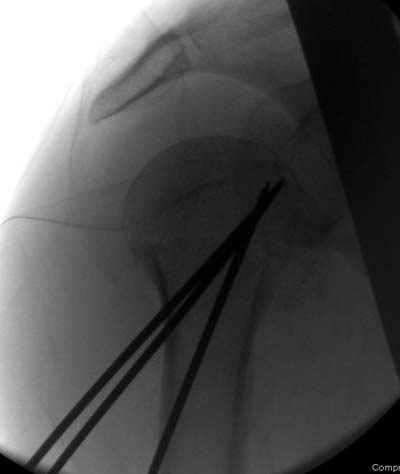

Здесь случай перелома-вывиха плеча, больному 56 лет, после "дважды" закрытой неудачной репозиции, опять же ургентно взяли в операционную, после полного общего обезболивания попытались сделать репозицию, и фиксацию провели спицами.

Больной находился в повязке, примерно напоминяющей косыночную, рекомендованы движения в локтевом суставе и маятниковые движения в плече, спицы удалены в три недели (были случаи миграции)

Больной амбулаторный, предупрежден на случай осложнения АВН головки.